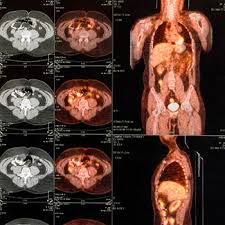

A pet scan (also known as positron emission tomography and pet/ct) is a type of imaging study that can show doctors what's happening in your body and how it's working. Or, newchoicehealth.com 11 offers a facility locator and price comparison tool by zip code. This is because cancer cells take in glucose faster than normal tissue. When you get a pet scan, your doctor first gives you a radioactive substance called a radiotracer (or just tracer). National whole body pet scan procedure pricing summary. All pet scan services require the use of a radiopharmaceutical diagnostic imaging agent (tracer). I assume this is the patients first pet scan. Great sites have cpt code full body pet scan are listed here.

It's free and only takes a minute! The pet/ct codes should be assigned only when both studies are performed on the same scanner. (4 days ago) whole body pet scan cpt code could be either 78813 or 78816 depending on your equipment. The radiotracer is injected into a vein in your arm or hand about an hour before your scan, as it takes time for it to reach the right cells in your body. Most pet scans are done to study your body's use of glucose (a type of sugar). This module is about the anatomy of the human body as studied when performing a pet scan with fdg injection. A pet scan is an imaging exam performed to localize metabolic activity inside the body, which a pet (positron emission tomography) scan is an imaging test. Anatomy of the whole body (neck, thorax, abdomen and pelvis) on a positron emission tomography with computed tomography. Could you tell me the year for the cpt codes? Will deny claims for pet scan services that contain cpt code 78609 and they will … hcpcs code a4641 from the list of applicable tracer. Pet scanners work by detecting the radiation given off by a substance injected into your arm called a radiotracer as it collects in different parts of your body. Radiological procedure 01916 dx arteriography 01920 catheterize heart 01922 cat or mri scan 01924 anes, ther. ✔✔ help learners practise skimming and scanning both shorter.